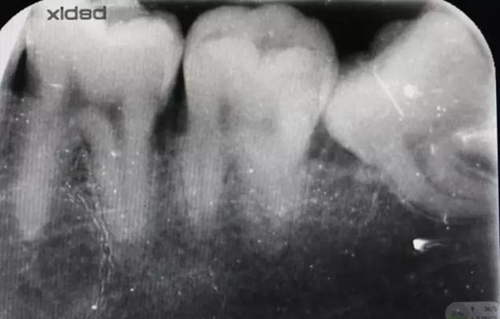

圖1.術(shù)前x線根尖片影像:38牙冠近中傾斜,雙根、近中根遠(yuǎn)中彎曲